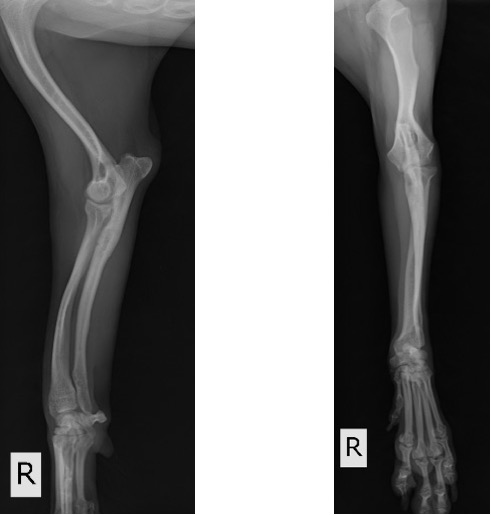

術後3ヵ月 (移植骨の癒合良好で、K-wireの刺入孔も不明瞭化してきました。)

術後6ヵ月 (骨切り線が完全に消失しました。)